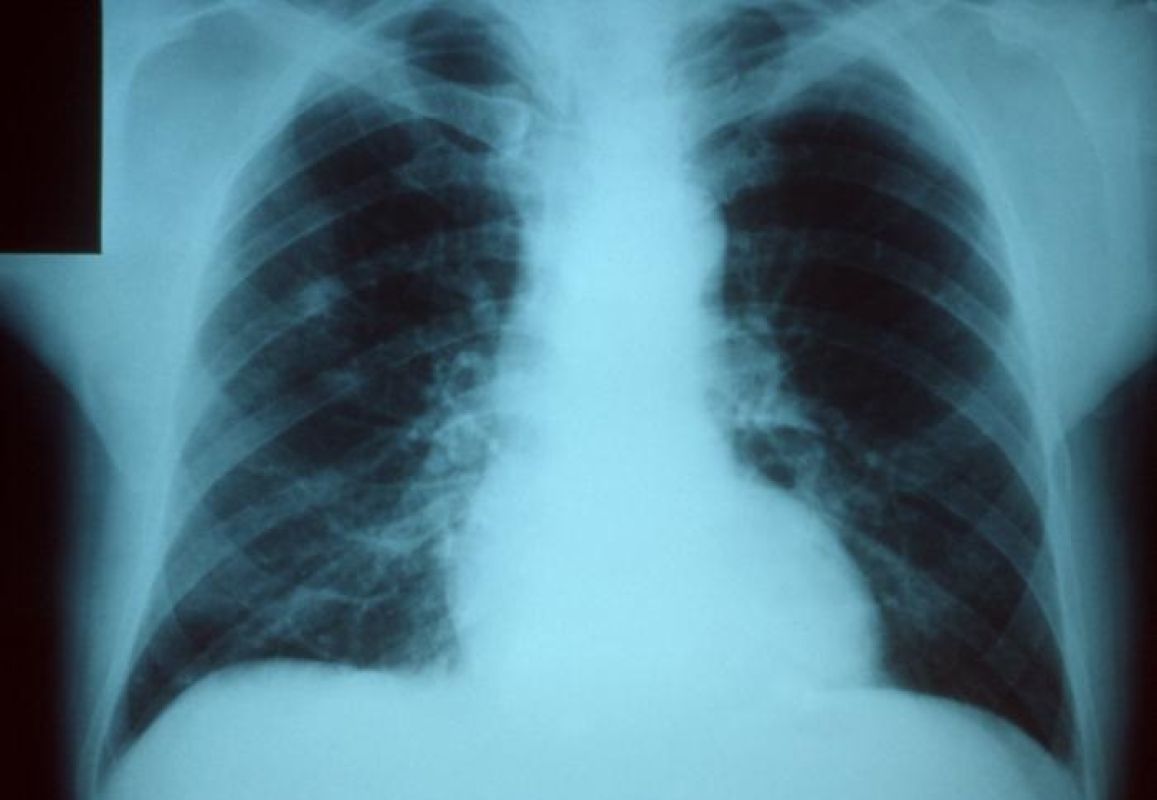

В Свердловске фиксируют рост заболеваемости пневмонией

Уровень общей заболеваемости ОРВИ в Свердловске и Свердловском районе на 15-й неделе 2022 года ниже эпидемического порога на 66,5 %.

За указанный период зарегистрировано 17 случаев внебольничной пневмонии: в возрастных категориях: 30-64 года - 6 человек; 65 и старше - 10 человек и детского населения в категории 5-14 лет - 1 ребенок. Госпитализировано 16 больных:  возрастом от 30 до 64 лет  - 5 человек,  возрастом от  65 и старше - 10 человек и детского населения от  5 до 14 лет - 1 ребенок.

В сравнении с предыдущей неделей текущего года заболеваемость внебольничной пневмонией повысилась на 13,3%.